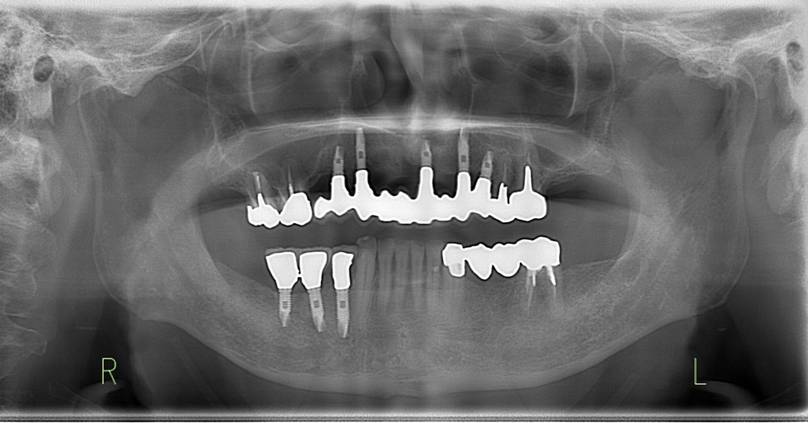

術前のパノラマレントゲン写真。仮歯を支えている4本の歯は根が残っているだけで抜歯の必要がありました。

63歳術後のパノラマレントゲン。インプラントはスプラインツイスト